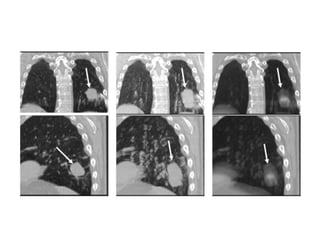

• 4D CT data are expressed as Maximum

Intensity Projection (MIP) and Average CT

image (AVE).

• MIP:

– Image formed with pixels (out of 8 set of data, if 8

gates are used) recording maximum CT number

(HU).

• AVE:

– Image formed with average CT numbers recorded

in each pixel throughout the acquisition.

• 4D PET:

– MIP images

– Summed images: Summing all the available data.

– Summed images are better, due to its less

susceptibility to noise.